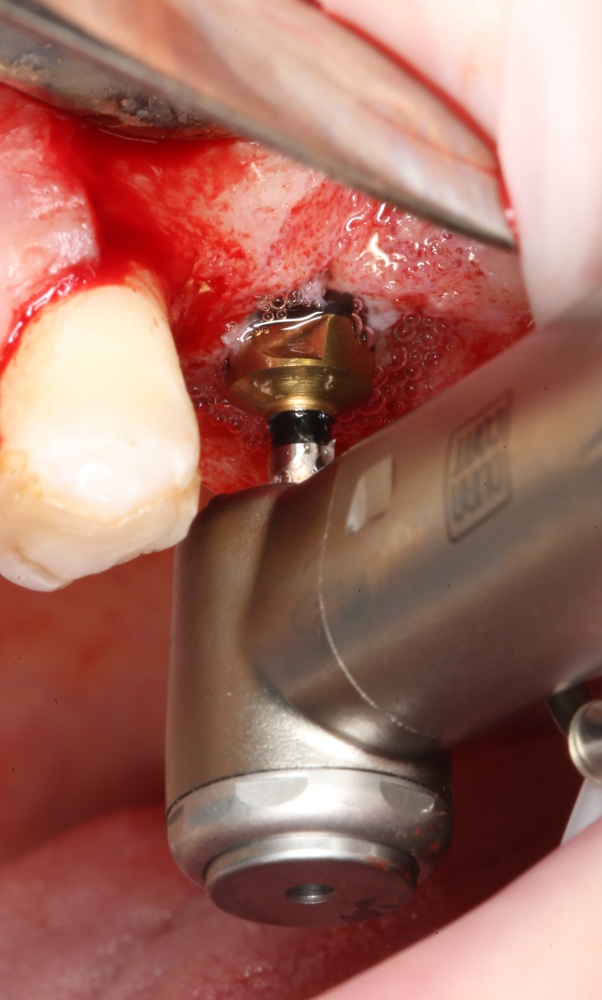

Выставляем обороты и крутящий момент на физиодиспенсере:

Напомню, что стартовать можно с любых оборотов, поскольку последующие фрезы «вырежут» всю поврежденную костную ткань. Кроме того, чем выше обороты, тем меньше вибрация фрезы и выше точность, начинать препарирование (сверление) кости при сложном рельефе альвеолярного гребня проще на максимальной частоте вращения.

В общем, мы с вами не придурки слесари-столяры, периимплантита не хотим, поэтому кортикальные фрезы не игнорируем:

Кортикальная фреза погружается строго до отметки (см выше). В нашем клиническом случае (с синуслифтингом) это особенно важно, чтобы имплантат не улетел в субантральное пространство. Таким образом получаем лунку, полностью конгруэнтную будущему имплантату. Это очень-очень важно: